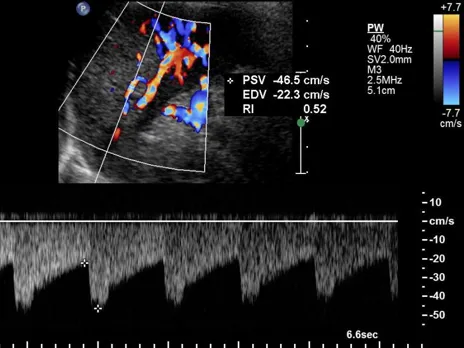

脉冲多普勒,正常脾脏,显示脾动脉搏动性血流曲线(图1,SA)和脾静脉连续性血流曲线(图2,SV)。